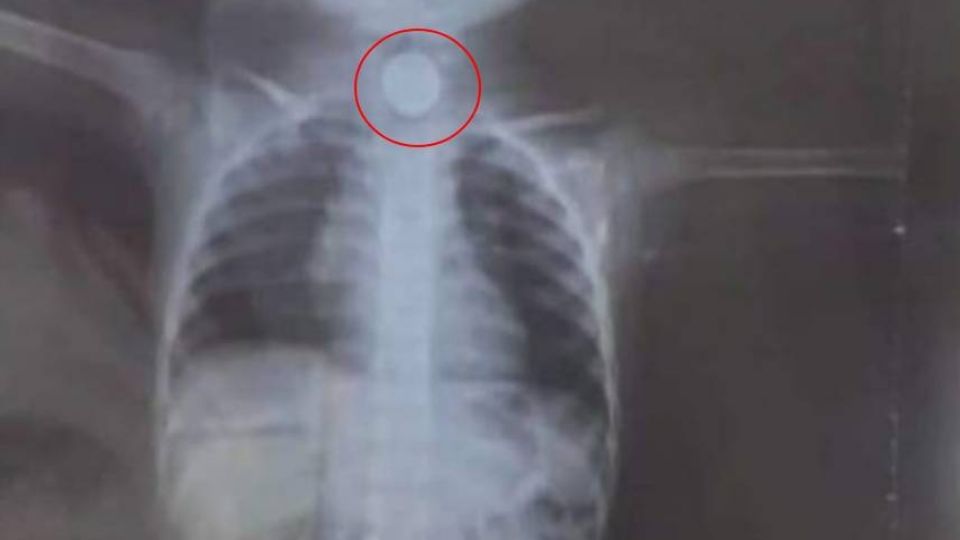

Niña de 2 años se traga pila y le explota en el cuerpo en Paraguay